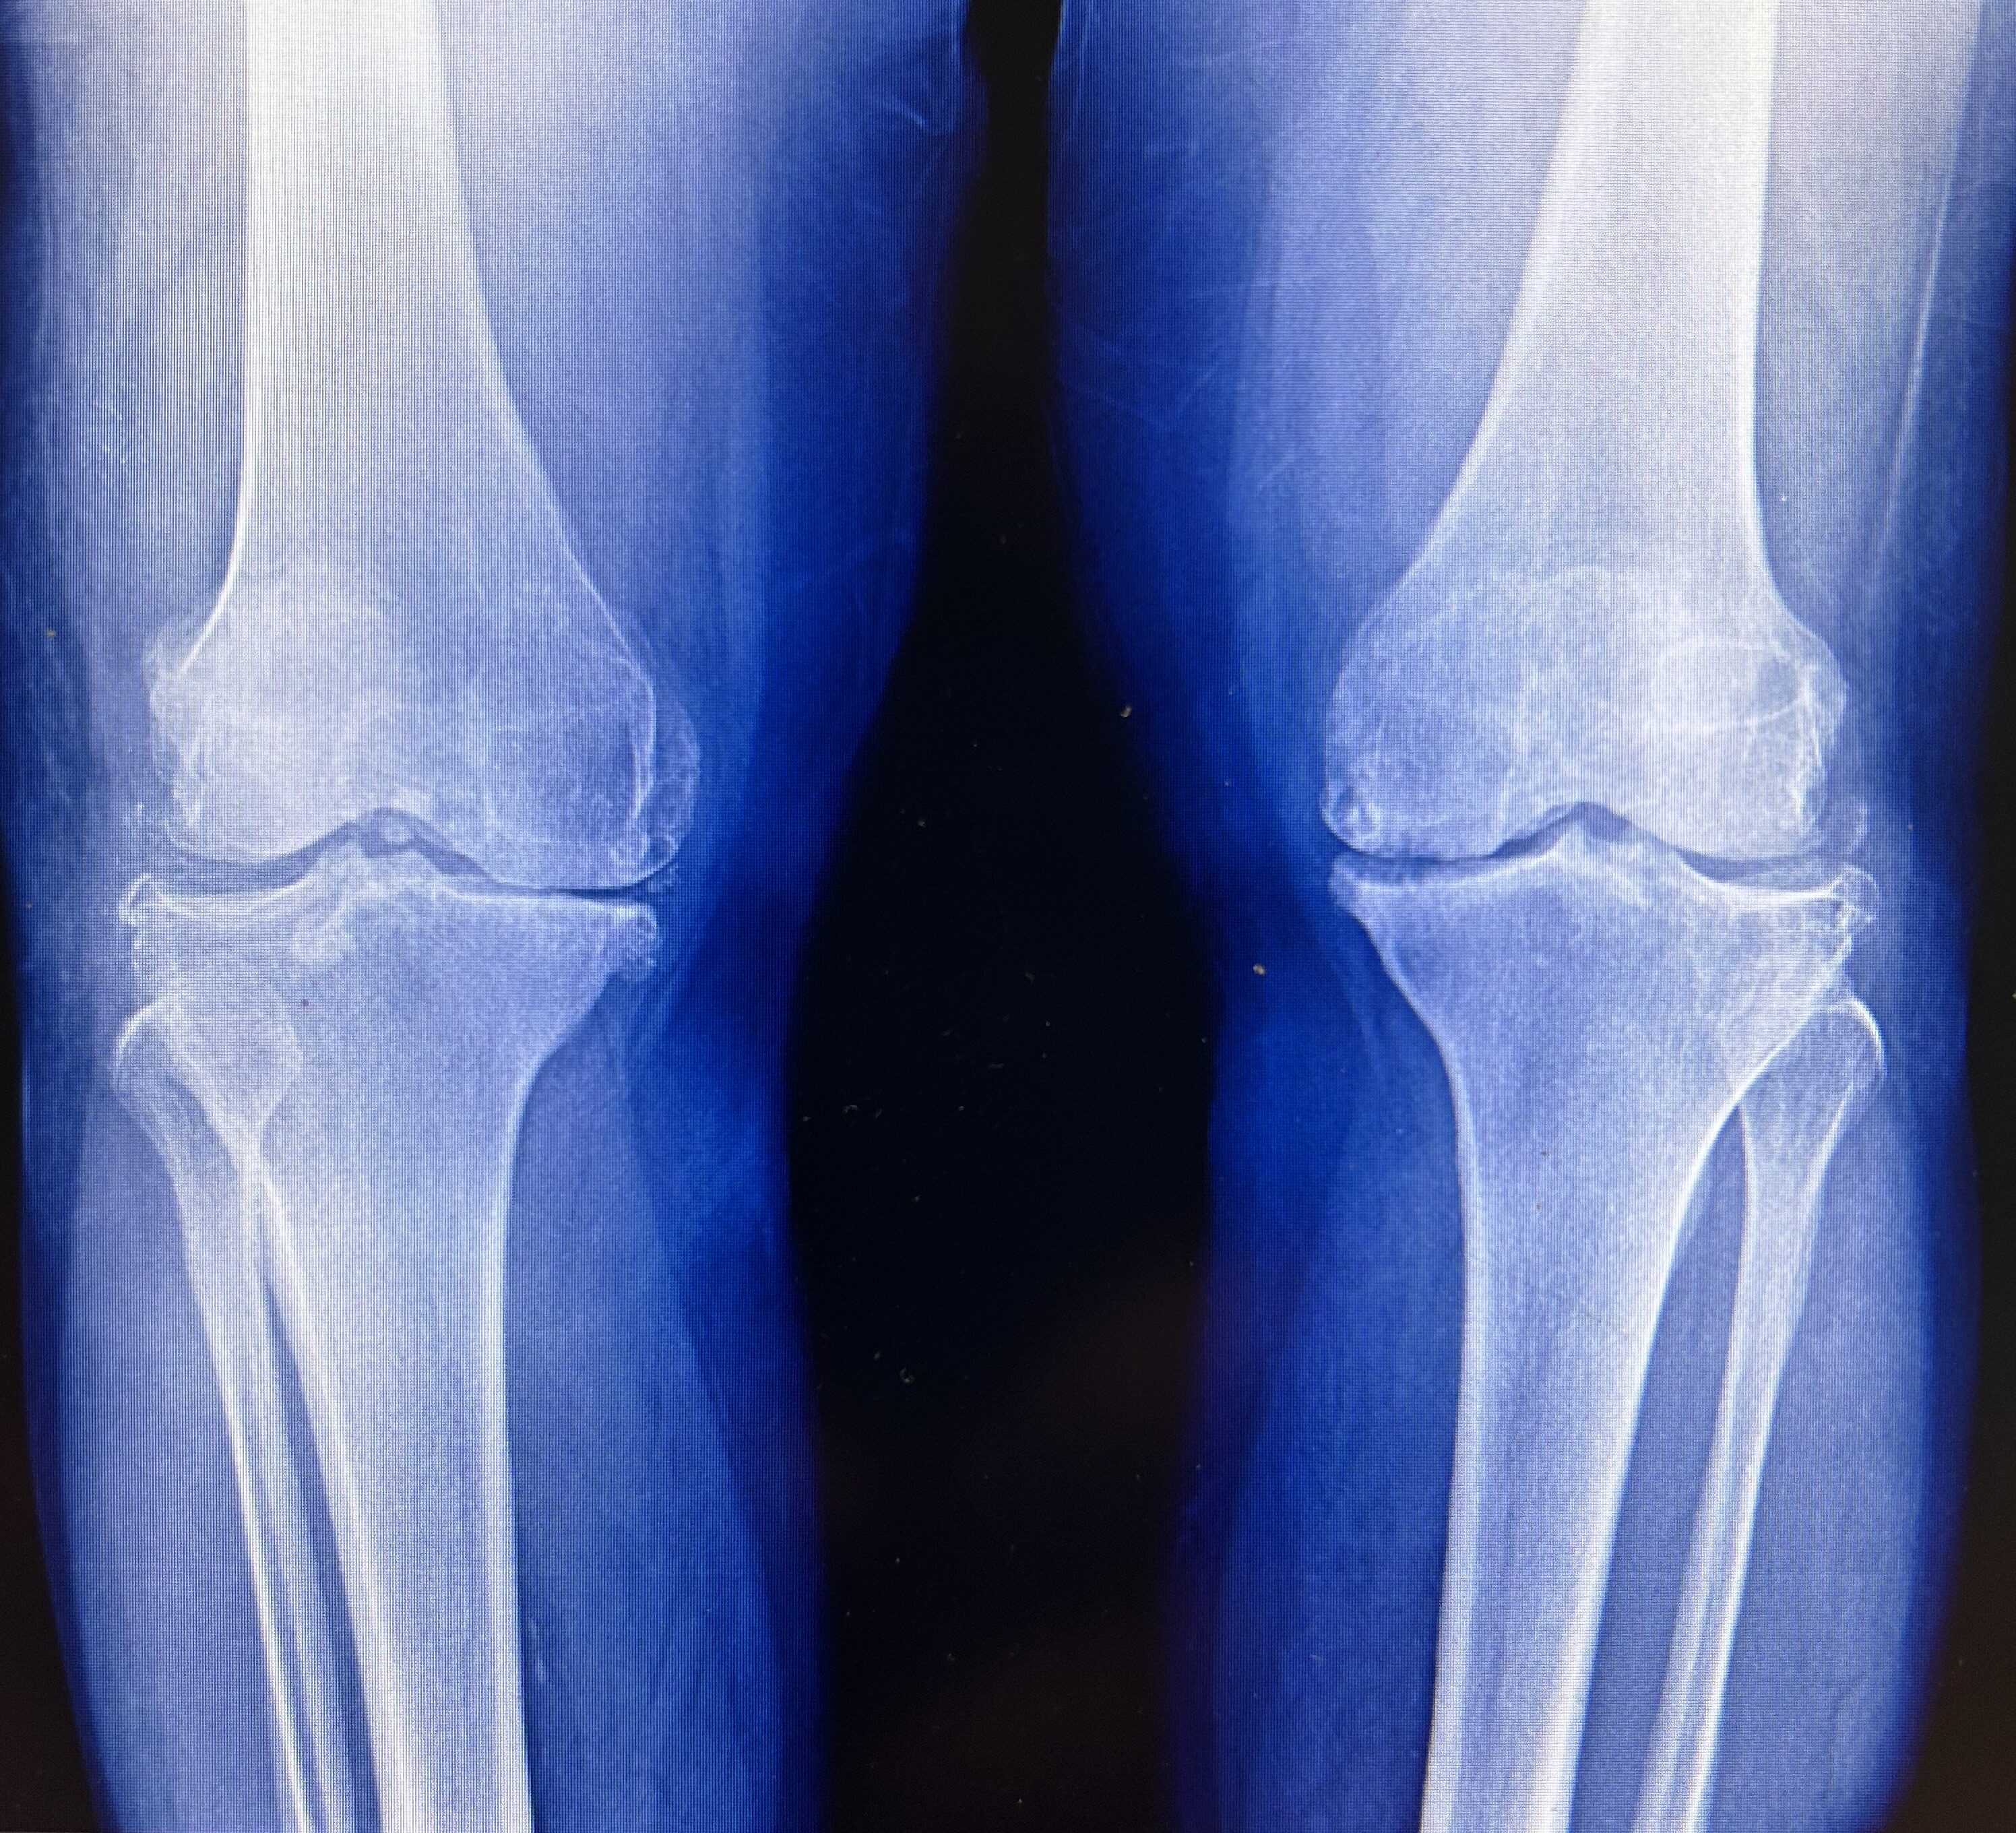

Группа корейских ученых привлекла 114 добровольцев с первичным остеартрозом коленного сустава. Диагноз всем им ставился по рентгеновским снимкам и наличию существенной боли при ходьбе. Участников разбили на три группы: первой колени облучали сверхмалыми дозами радиации (шесть сеансов по 0,05 грея), второй — малыми (то же число сеансов по 0,5 грея), третью не облучали ничем. Вторая группа получила локальное облучение, сравнимое с 30 тысячами рентгеновскими снимками груди или 420 компьютерными томографиями грудной клетки. О результатах исследователи отчитались на ежегодном собрании Американского общества радиотерапии.